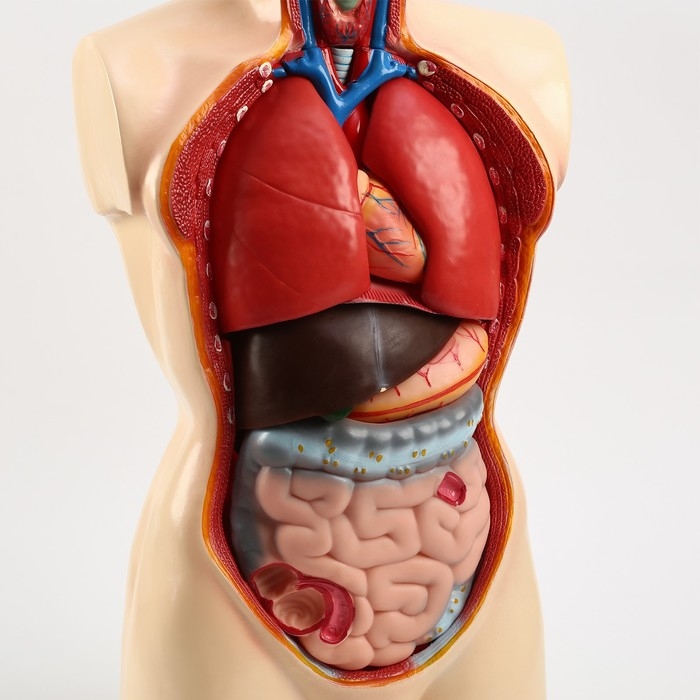

Анатомические модели

ЕКБ 93

No Brand, артикул: 7072363